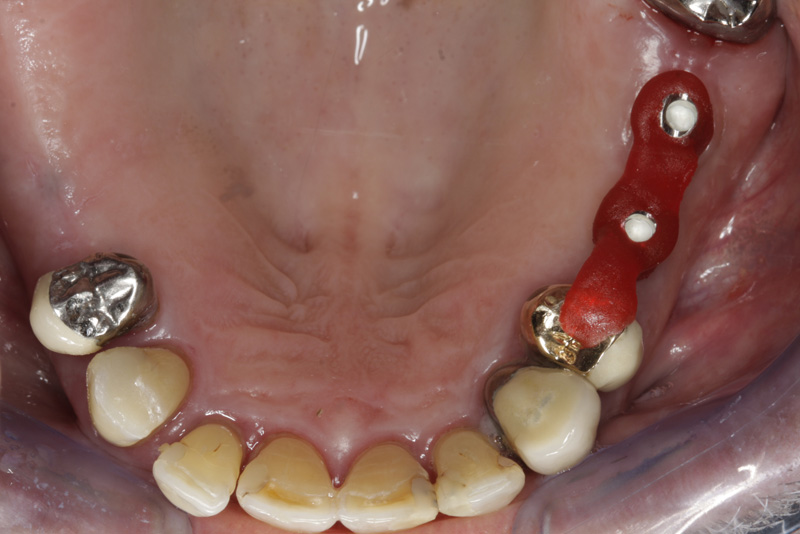

V případě chybění většího počtu zubů v postranních úsecích čelistí je možné ošetření pomocí implantátů, které nahradí ošetření pomocí snímacích náhrad kotvených na zbývajících zubech nebo patře.

Podmínkou je opět dostatečné množství kosti.

Protetické řešení může být pomocí můstku, který je kotvený na implantátech nebo pomocí jednotlivých korunek na implantátech.

V zásadě je možné do těchto můstků zařadit i přirozené zuby, zejména pokud je potřeba tyto zuby ošetřit proteticky - korunkami. Korunky nebo můstky mohou být na implantáty nacementovány nebo přišroubovány.

Zdravé zuby zůstanou zachovány a přitom náhrady jsou pevné, jako na vlastních zubech